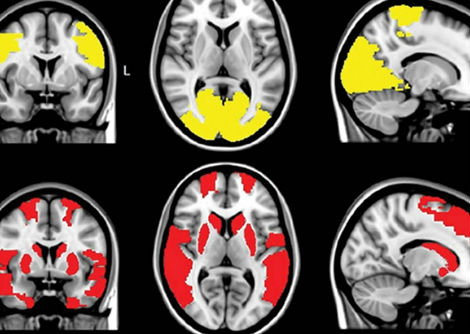

ضمّت المجموعة السريرية 70 مريضاً مصابين بمتلازمة POH-VAU، أُثبتت لديهم التحولات المصلية (Seroconversion) تجاه CMNV. يُعرَّف التحول المصلي بظهور أجسام مضادة نوعية ضد الفيروس في مصل الدم، مما يدل على عدوى نشطة أو حديثة. والأهم من ذلك، أنه جرى الكشف عن المادة الجينومية للفيروس مباشرةً داخل الأنسجة العينية، مما يُثبت أن الفيروس لم يكتفِ بالدوران في مجرى الدم، بل تكاثر بفاعلية داخل العين. عانى المرضى المصابون من نوبات متكررة من التهاب العنبية الأمامي مع ارتفاع ضغط عيني عصيٍّ على العلاجات التقليدية، مما يُشير إلى آلية التهابية مزمنة ذات منشأ فيروسي. ويُثير هذا الاكتشاف احتمال أن تكون بعض حالات الزرق الالتهابي غير المُفسَّرة أو المقاوم للعلاج ناجمةً عن مسببات فيروسية لم تُكشَف بعد.